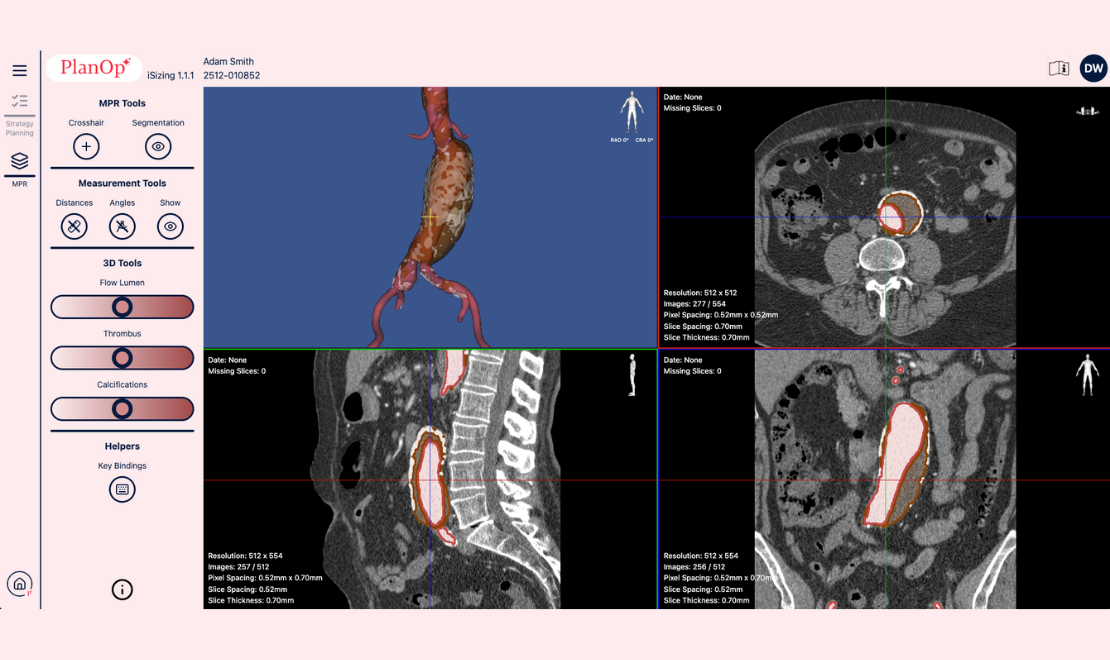

Upload CT Scan & Visualise using MPR Viewer

To begin autosizing, simply upload the patientβs CT scan and instantly visualise the anatomy using the MPR Viewer. iSizing enables side-by-side comparison of the patient anatomy with a 3D model, providing a comprehensive anatomical overview.

Automated segmentation & Sizing measurements

iSizing performs fully automated segmentation including: Flow lumen, Thrombus, Calcifications. Additionally, iSizing also offers automated sizing measurements like baselines, lengths, and aortic diameters.β